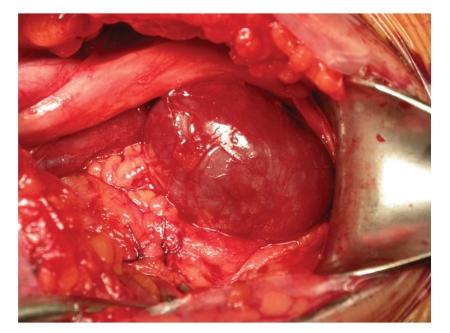

We report a case of a 21-year-old man with a popliteal venous aneurysm of the left popliteal fossa, with local symptoms and pain during palpation. Early diagnosis is fundamental in order to prevent the thromboembolic events or other major complications. Duplex scanning, Computed Tomography scanning, and Magnetic Resonance imaging are considered to be important non-invasive diagnostic methods for the diagnosis of PVA. The Angio Computed Tomography acquisition confirmed a 36 mm x 17 mm oval mass in the left popliteal fossa continuous with the popliteal veins. This lesion had presented contrast enhancement only in delayed acquisition (180 sec) and so appeared to be a true venous aneurysm and no arterial. The PVA was repaired surgically via a posterior approach to the popliteal fossa. A 4 x 2 aneurysm was identified. In the same time open tangential aneurysmectomy and lateral vein reconstruction were realised. This case is interesting because the Angio Computed Tomography study, in delayed acquisition, has allowed a correct diagnostic assessment of PVA and the surgical treatment.

我们报告一例21岁男性患者,其左腘窝患有腘静脉瘤,伴有局部症状及触诊疼痛。早期诊断对于预防血栓栓塞事件或其他严重并发症至关重要。双功扫描、计算机断层扫描和磁共振成像被认为是诊断腘静脉瘤的重要无创诊断方法。血管计算机断层扫描成像证实左腘窝有一个36毫米×17毫米的椭圆形肿块,与腘静脉相连。该病变仅在延迟采集(180秒)时出现对比增强,因此似乎是一个真正的静脉瘤而非动脉瘤。通过腘窝后方入路对腘静脉瘤进行了手术修复。发现一个4×2的动脉瘤。同时进行了开放性切线动脉瘤切除术和外侧静脉重建。该病例很有意思,因为血管计算机断层扫描研究在延迟采集时能够对腘静脉瘤进行正确的诊断评估并指导手术治疗。